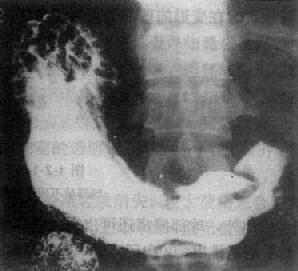

組織病理:來自大腸的皮膚轉移癌主要為分泌良好的分泌黏蛋白的腺癌有些病例呈黏蛋白癌外觀。皮膚轉移癌呈低分化者較少見偶亦見皮膚轉移癌間變十分明顯,以致難以辨認其為上皮起源。來自胃的皮膚轉移癌常呈間變性浸潤癌呈數量不等的含有細胞內黏蛋白的印戒狀細胞位於疏鬆或纖維性基質中。